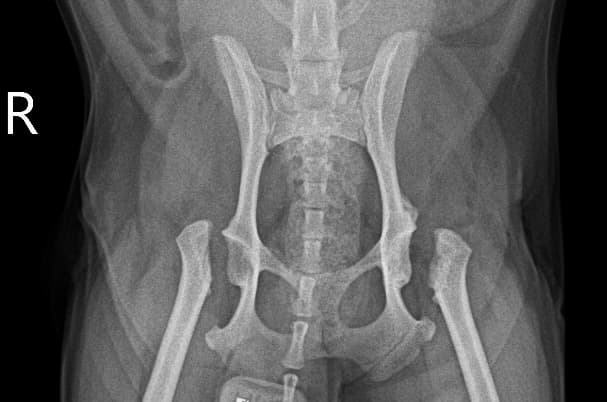

정형외과 전공의 수의사가 직접 수술합니다.

0164 채널 CT 촬영을 통해서 신속하게 고화질 영상을 얻어, 종양 유래 확인 및 전이 평가, 간문맥단락증(PSS), 선천적 뼈 기형과 같은 심화된 진단을 할 수 있습니다.

02C-arm을 통해서 좀 더 섬세한 정형외과 수술을 진행하고, 본원에서는 외과적 침습을 최소화 하는 중재적 시술 (기관 협착, 동맥관개존증(PDA), SUB 등)을 진행하고 있습니다.

13수술 중 골절 상태 혹은 이식물 적용 후 상태 등 육안으로 명확히 확인하기 힘든 상태를 X-ray 확인하여 정확한 수술 결과를 만들어 내는 것이 가능